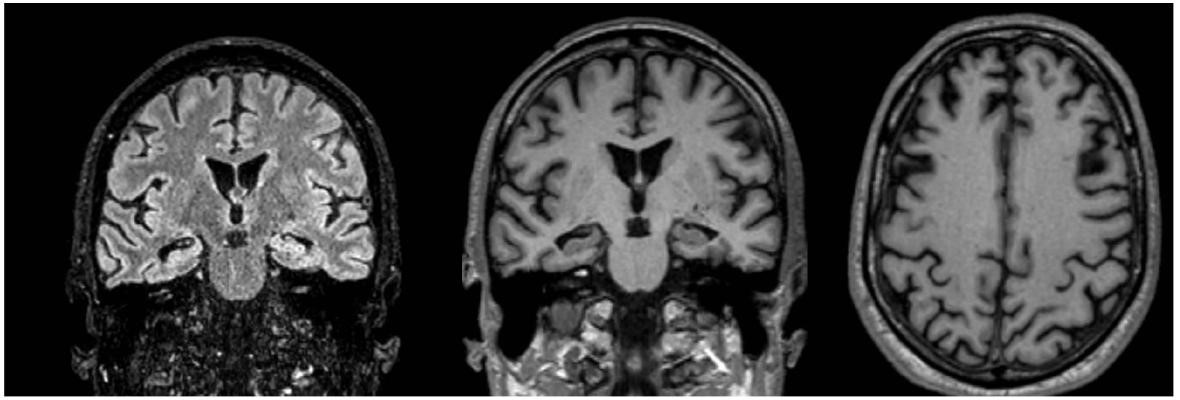

El primer paciente masculino de 65 años presentaba trastornos mnésicos con Mini-mental test 24 puntos. Se analizaron las imágenes convencionales, que no mostraban signos de leucopatía (Fazekas, grado 0), ni hidrocefalia (Evans 0.2), ligera atrofia temporal (MTA, grado 2), sutil atrofia global (GCA, grado 1) (Koedam, grado 1) (Figuras 7 y 8).

En el reporte de Inteligencia artificial, el volumen de sustancia gris de los lóbulos parietal y frontal se encontró por debajo del percentil 1 y 5 % para el grupo etario. El volumen de ambos hipocampos se encontró por debajo del percentil 1% para el grupo etario (Figura 1).

Figura 7: Resonancia magnética de cerebro. Corte axial Flair

Parénquima cerebral sin particularidades. No se observan signos de leucopatía ni lesiones ocupantes de espacio.

Figura 8: Resonancia magnética de cerebro. Corte coronal flair y T1. Axial T1.

Signos discretos de atrofia temporal profunda (MTA -Scheltens grado 2). Axial T1: signos discretos de atrofia global (CGA grado 1 y Koedam grado 1).